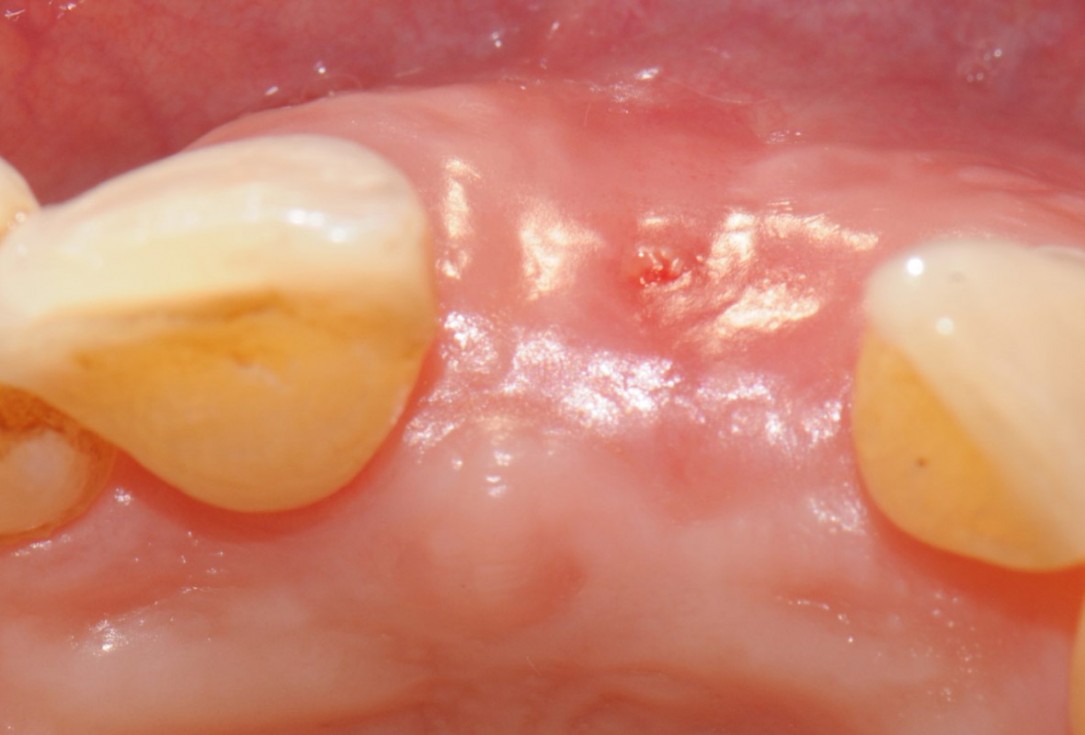

15/18 - 20 weeks after surgery perfect aesthetic integration of newly formed keratinized tissue with surrounding tissueTooth extraction and socket sealing with mucoderm® - Dr. A. Rossi

16/18 - Implant placementTooth extraction and socket sealing with mucoderm® - Dr. A. Rossi